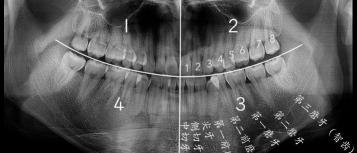

智齿是从正中的门牙往里数第八颗牙齿,也就是第三颗磨牙。它是发育、萌出最晚的牙齿,通常在4~5岁时形成牙胚,随后逐渐发育形成牙齿,一般17~25岁左右萌出,此时人的生理、心理发育都接近成熟,因此俗称“智齿”。

智齿的形态也是各种各样,基本罗列如下几种,实际会有更多复杂情况。

智齿位置、结构、生长形态各不相同,这也直接导致拔除的难易程度各不相等。